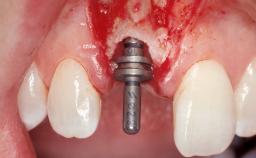

A 30-year-old female patient had lost tooth 21 and was referred to our clinic for consultation and treatment. Due to advanced apical infection, tooth 21 had been extracted two months earlier at another clinic and an acrylic-resin tooth had been bonded to the adjacent teeth. The patient desired implant treatment to avoid any damage to the adjacent natural teeth. While the patient had no history of any systemic disorder, she was a heavy smoker and exhibited medium to advanced periodontitis in the entire jaw. After the initial treatment to achieve a pocket probing depth of less than 4 mm and no bleeding on probing, a decrease in the height of the papillae mesial and distal to the extraction site and overall gingival recession were observed.

Type of Implants One-Piece|Reduced-Diameter

Soft Tissue Grafting Simultaneous

Placement Protocol Early or late implant placement